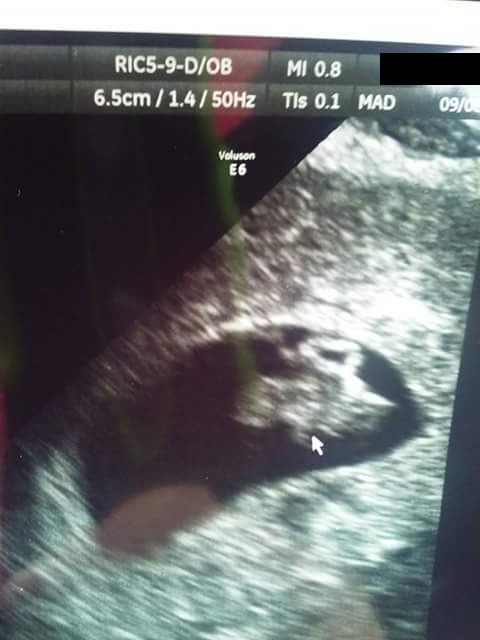

Here we are!!! I've been so excited to post this. My rainbow baby at 8w2d. Measured exactly as we thought with 165bpm. Baby looks a bit like a Lego character so I'm picturing "everything is awesome" playing on repeat as baby grows!!! Due April 13!